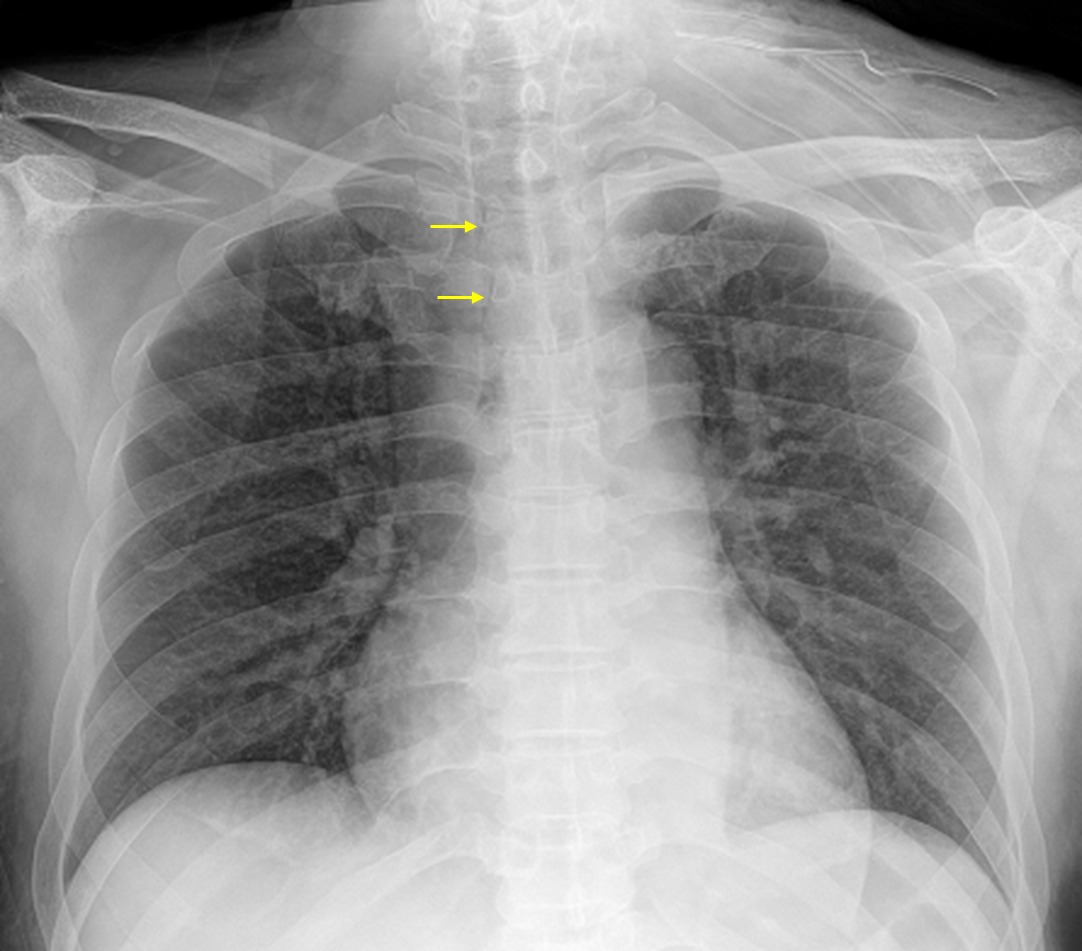

54세 남자가 3일 전부터 가슴과 목이 아파서 병원에 왔다. 7일 전 심한 구토 이후 입안과 목 부위가 아프고 침을 삼킬 때 불편했다고 한다. 비흡연자이다. 혈압 114/70 mmHg, 맥박 86회/분, 호흡 18회/분, 체온 38.1℃이다. 앞 목은 부어 있고 누르면 아파하였다. 가슴 청진에서 호흡음은 정상이다. 가슴 X선사진과 가슴 컴퓨터단층촬영 사진이다. 혈액검사 결과는 다음과 같다. 진단은?

Img | CXR: Rt. paratracheal hypolucency, suggesting pneumomediastinum CT: Mediastinal inflammation, gas bubbles |

• CXR상 trachea 우측에 air로 추정되는 저음영이 관찰되는데, 이는 pneumomediastinum을 시사한다. 식도 파열에 의해 pneumomediastinum이 발생할 수 있다. 양쪽 폐실질에는 특이사항이 없으나 CT에서 종격동에 염증에 의한 것으로 보이는 fluid collection과 gas bubble이 보이기 때문에 급성 종격동염으로 진단할 수 있다.